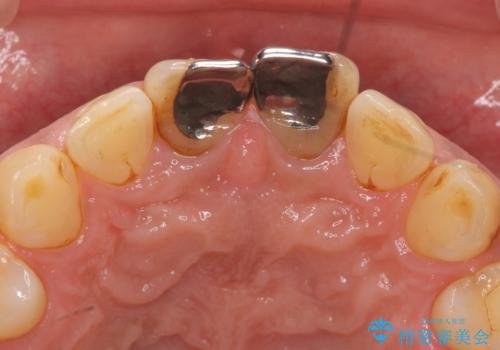

歯ぐきからの出血 膿が出る 前歯根管・セラミック治療

- 体調により前歯部の歯ぐきから出血や膿が出ることの改善を求めて来院されました。

X線写真より、根尖部に透過像が認められ根管治療・ファイバーコア築盛・セラミッククラウンの作製が必要な状態です。

- 46万円(仮歯・根管治療・ファイバーコア・ジルコニアクラウン×2)費用は治療当時の料金となります